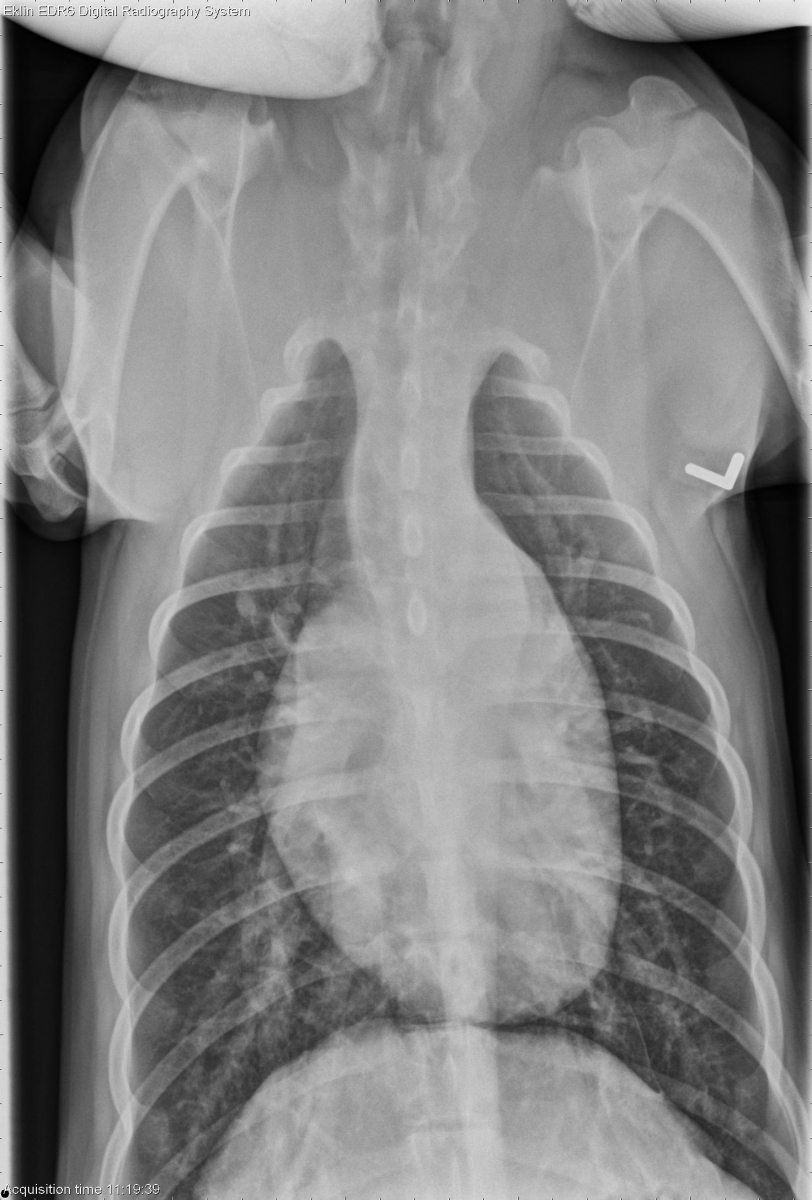

Today’s case is an 8 month old female Beagle with 5/6 continuous heart murmur. What are your findings?

DV Thorax

On lateral radiographs, the left side of the heart is enlarged. The left atrium is visible as a triangular soft tissue opacity on the lateral view, and as a double density sign on the d/v.

On the d/v, the aorta has a prominent bulge at one o’clock, and the pulmonary artery is enlarged at two o’clock. The left auricle is also causing a slight bulge in the cardiac silhouette at the three o’clock position.

There is a prominent vascular pulmonary pattern with enlarged pulmonary arteries and veins throughout the lungs.

Left-to-right patent ductus arteriosus (PDA)

Echocardiogram showed the presence of a PDA with a dilated left ventricle and atrium and mild mitral regurgitation. The PDA allows high pressure blood to flow into the pulmonary artery, causing overcirculation of the lungs and volume overload of the heart. The bulges at the 1, 2, and 3 o’clock positions are characteristic of PDA.